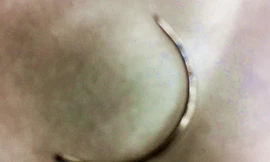

Các y, bác sĩ Bệnh viện Mắt Huế phẫu thuật lấy chiếc kim khâu dài 1cm bị "bỏ quên" 2 năm trong mí mắt một người phụ nữ ở Huế.

Phát hiện kim khâu ‘quên’ trong mí mắt 2 năm trời

TPO - Do mí mắt bị “lỗi” cần phẫu thuật điều chỉnh, một phụ nữ tại Huế đến bệnh viện phẫu thuật can thiệp thì được bác sĩ phát hiện có một chiếc kim khâu bị bỏ “quên” trong mí mắt gần 2 năm trời, trong lần người này đi làm đẹp ở một cơ sở thẩm mỹ.